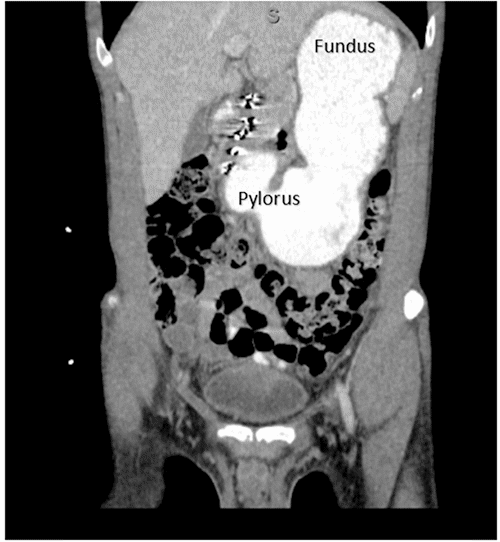

A 24-year-old man with a history of duodenal ulcer and delayed gastric emptying presented multiple times in the last three years to the emergency department (ED) for postprandial abdominal pain associated with nausea, vomiting and progressive intolerance to solids. During his most recent admission to the ED, his BMI was 18 kg/m2. A computed tomography (CT) scan of the abdomen and pelvis with contrast revealed narrowing of the aortomesenteric angle, measuring 11.3 degrees, and an aortomesenteric distance of 5.4 mm (Figure 1).

Figure 1. CT Scan of Abdomen and Pelvis with PO and IV Contrast. Published with Permission

The abdominal CT also revealed distension of the stomach and occipital duodenum (Figure 2) and duodenum decompression as it passes between the aorta and SMA, findings consistent with SMA syndrome diagnosis.

Figure 2. CT Scan of Abdomen and Pelvis with PO and IV Contrast Showing Severe Distention of Stomach. Published with Permission